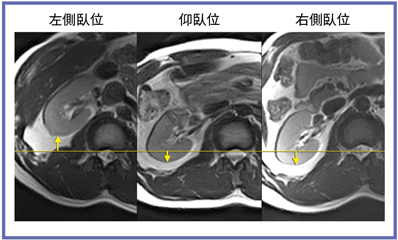

術前の画像検査は仰臥位で行われるため,手術の際の体位の違いによる乖離が問題となっていた。Titan 3Tの71cmオープンボアによって,仰臥位と左右側臥位で撮像を行い,腎臓および腎血管の移動・偏位を比較してみた(図5)。腎動脈は,大動脈からの分岐角が仰臥位と側臥位では大きく変わっていることが観察できる(図6)。また,腎臓も同様に,側臥位で上となる側の腎が,腹側へ偏位していた(図7)。

![]() 図7 検査体位による腎臓の偏位(右腎) |